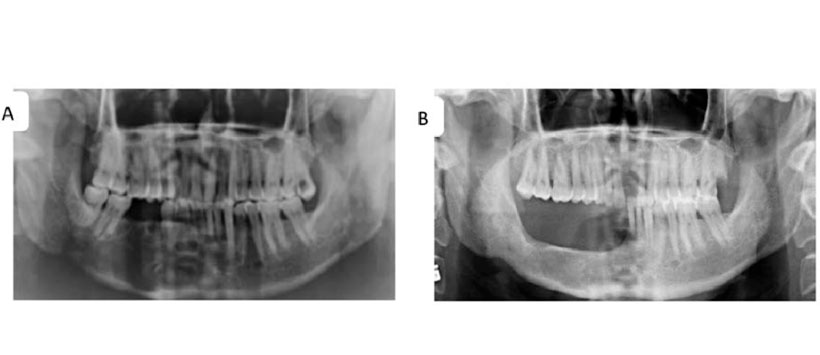

- Figura 3: Mandibulectomía marginal de un Queratoquiste recurrente de la mandíbula derecha. (A) Radiografía panorámica muestra múltiples lóculos con una delgada línea esclerótica en el hueso alveolar de los dientes anteriores mandibulares derechos, el segundo premolar y los primeros sitios de extracción molar, lo que indica recurrencias. (B) Radiografía panorámica luego 18 meses después de la cirugía.